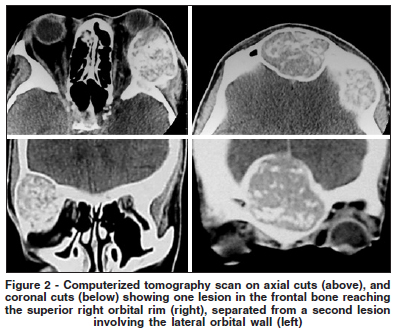

On examination her best corrected visual acuity was 20/20 in the right eye (OD) and 20/30 in the left (OS). There was 6 mm of proptosis and downward deviation of the OD (Figure 1). Upgaze and right gaze were moderately restricted. Slit lamp examination, pupillary reactions and intraocular pressure measurements were normal. Fundus examination revealed marked atherosclerotic changes of the vessels in both eyes more prominent in OS. A firm, nontender mass was present in the right superolateral orbit and another one in the middle of the frontal bone, reaching the orbital rim. A computerized tomography scan showed two separate mostly hyperdense and well-circumscribed lesions in the right orbit. Both lesions were heterogeneous with hyperdense areas intermingled with some normal or hypodense areas. The lateral wall lesion was very large, with partial erosion of its lateral and medial limits extending medially to the orbit and laterally to the temporal fossa (Figure 2). A biopsy was performed through a lateral skin incision revealing a firm and multilobular tumor. Histopathologic examination revealed a tumor composed of a uniform distribution of multinucleated giant cells in a background of fibrovascular proliferation. There was fibrous proliferation associated with osseous metaplasia and osteoclastic activity in the tumor. The diagnosis was consistent with brown tumor. In order to control the hyperparathyroidism, the patient was submitted to surgical removal of the parathyroid glands with marked improvement in her condition. The orbital lesions progressively reduced in size and the pain disappeared. There was marked regression in the proptosis of the right eye.